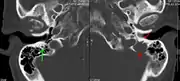

A CT of the brain revealed a lytic lesion in the left temporal bone (right side of image), and petrous temporal bones involving the mastoid segment of the facial nerve canal. Red arrows: lesion; green arrow: normal contralateral facial nerve canal. The lesions are consistent with a myeloma deposit.